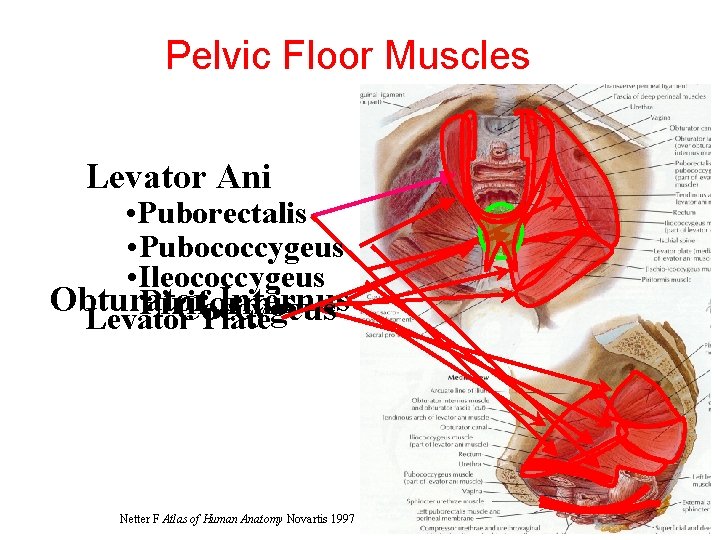

Pelvic Floor Muscles Levator Ani • Puborectalis • Pubococcygeus • Ileococcygeus Obturator Internus Piriformis Coccygeus Levator Plate Netter F Atlas of Human Anatomy Novartis 1997